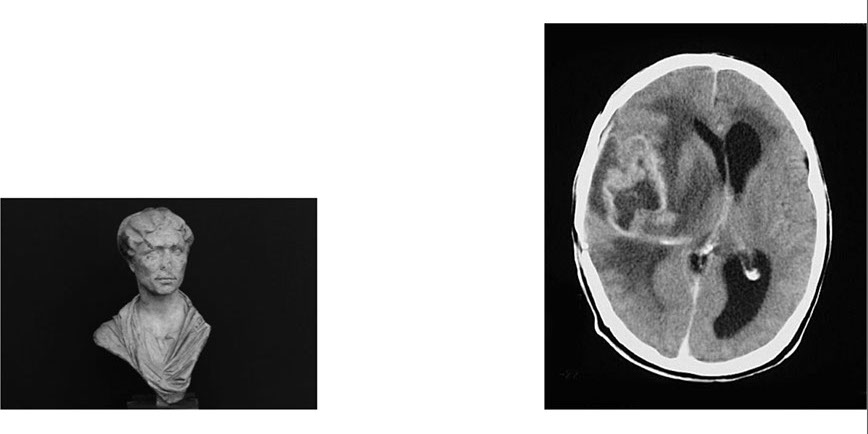

El proyecto "Memorias de un Sujeto" surge a partir de un estudio sobre el olvido y el recuerdo, y se presenta como una transcripción de referencias visuales y conexiones entre imágenes que conforman un código de memoria.

Se trata de un trabajo de posproducción en el cual las imágenes se reúnen y se abordan como un archivo, codificando e interpretando cada conexión. "Memorias de un Sujeto" investiga la forma en que la mente relaciona, reemplaza o construye nuevas imágenes a través de recuerdos pasados. La vista de dos guardias montados en un parque de Londres puede hacer referencia a un recuerdo de la infancia de un padre montando a caballo con un amigo en el campo, un hecho aparentemente sin relación pero que ha permitido de manera casi inconsciente tomar y procesar esa nueva fotografía, un hecho aislado que de repente adquiere valor.

El proyecto tiene un sentido más amplio sobre cómo se aborda directamente la memoria y cómo afecta al trabajo creativo. La memoria como una herramienta que permite crear nuevas imágenes que se fusionan entre sí. Reemplazándose, reformándose y sintiéndose reemplazadas por una cantidad de nuevas imágenes, superponiéndose unas a otras pero con un punto de origen común que sirve como unión.